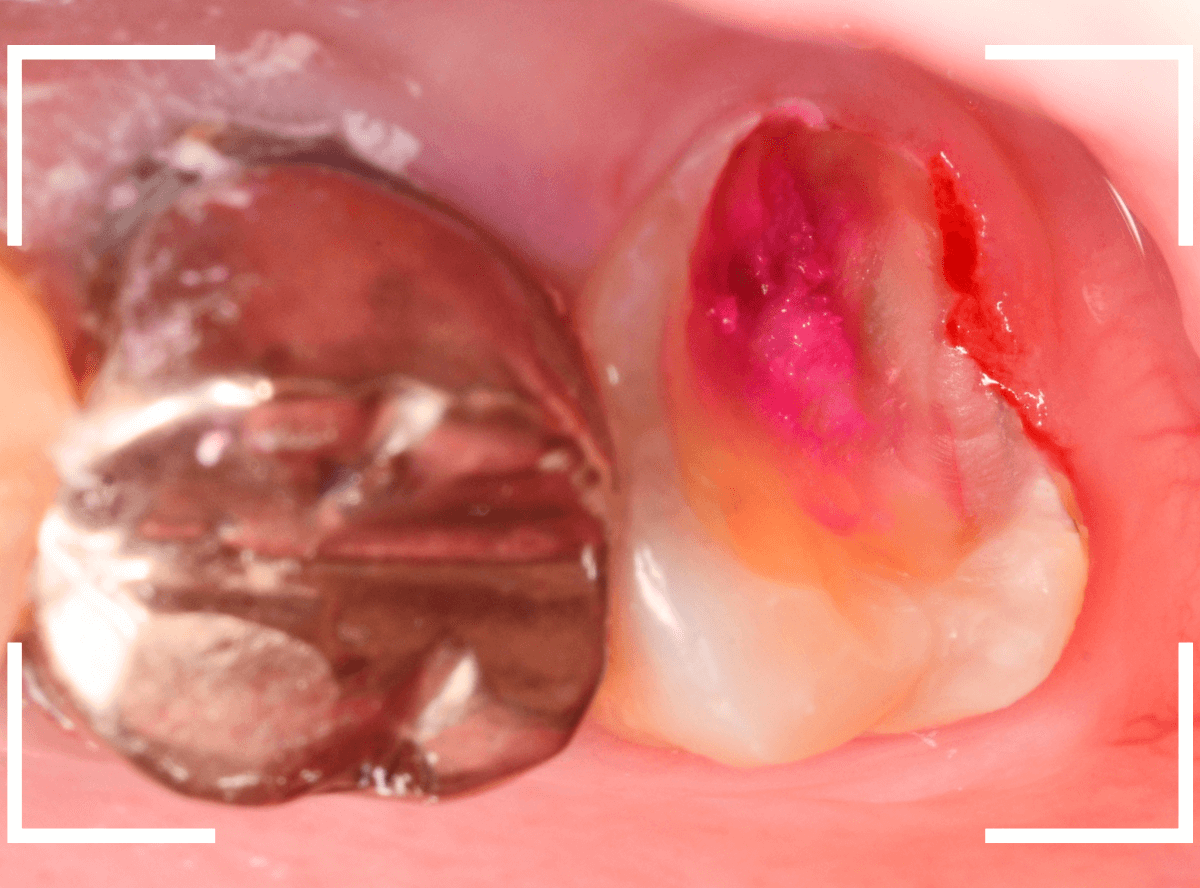

Case.12 下の一番奥の歯が、奥からひどい虫歯

「下の一番奥の歯が痛い」という訴えで来院された患者さんの例です。

一見では、特に問題ないように見えます。

治療を開始します。

歯の奥の部分を少し削ると、虫歯が出てきました。

慎重に虫歯を除去します。

歯肉ラインの下まで虫歯が進行しているため、虫歯の上に歯肉が広がっており、虫歯の見分けがつきづらい状況になっています。

虫歯を取り残さないように、余分な歯肉を除去します。

電気メスで、虫歯周囲の歯肉を除去後、全ての虫歯を除去しました。

虫歯は深かったですが、なんとか神経寸前のところで食い止められました。

神経を保護するお薬をつめて、セメントで蓋をしてしばらく経過観察します。

経過観察後、痛みがない事が確認できれば、つめものを作製します。